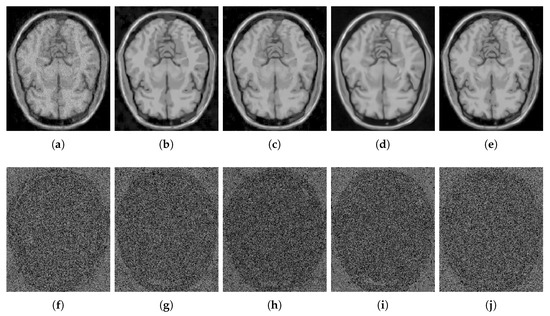

4.2.1. Synthetic Data

4.2.2. Real Data